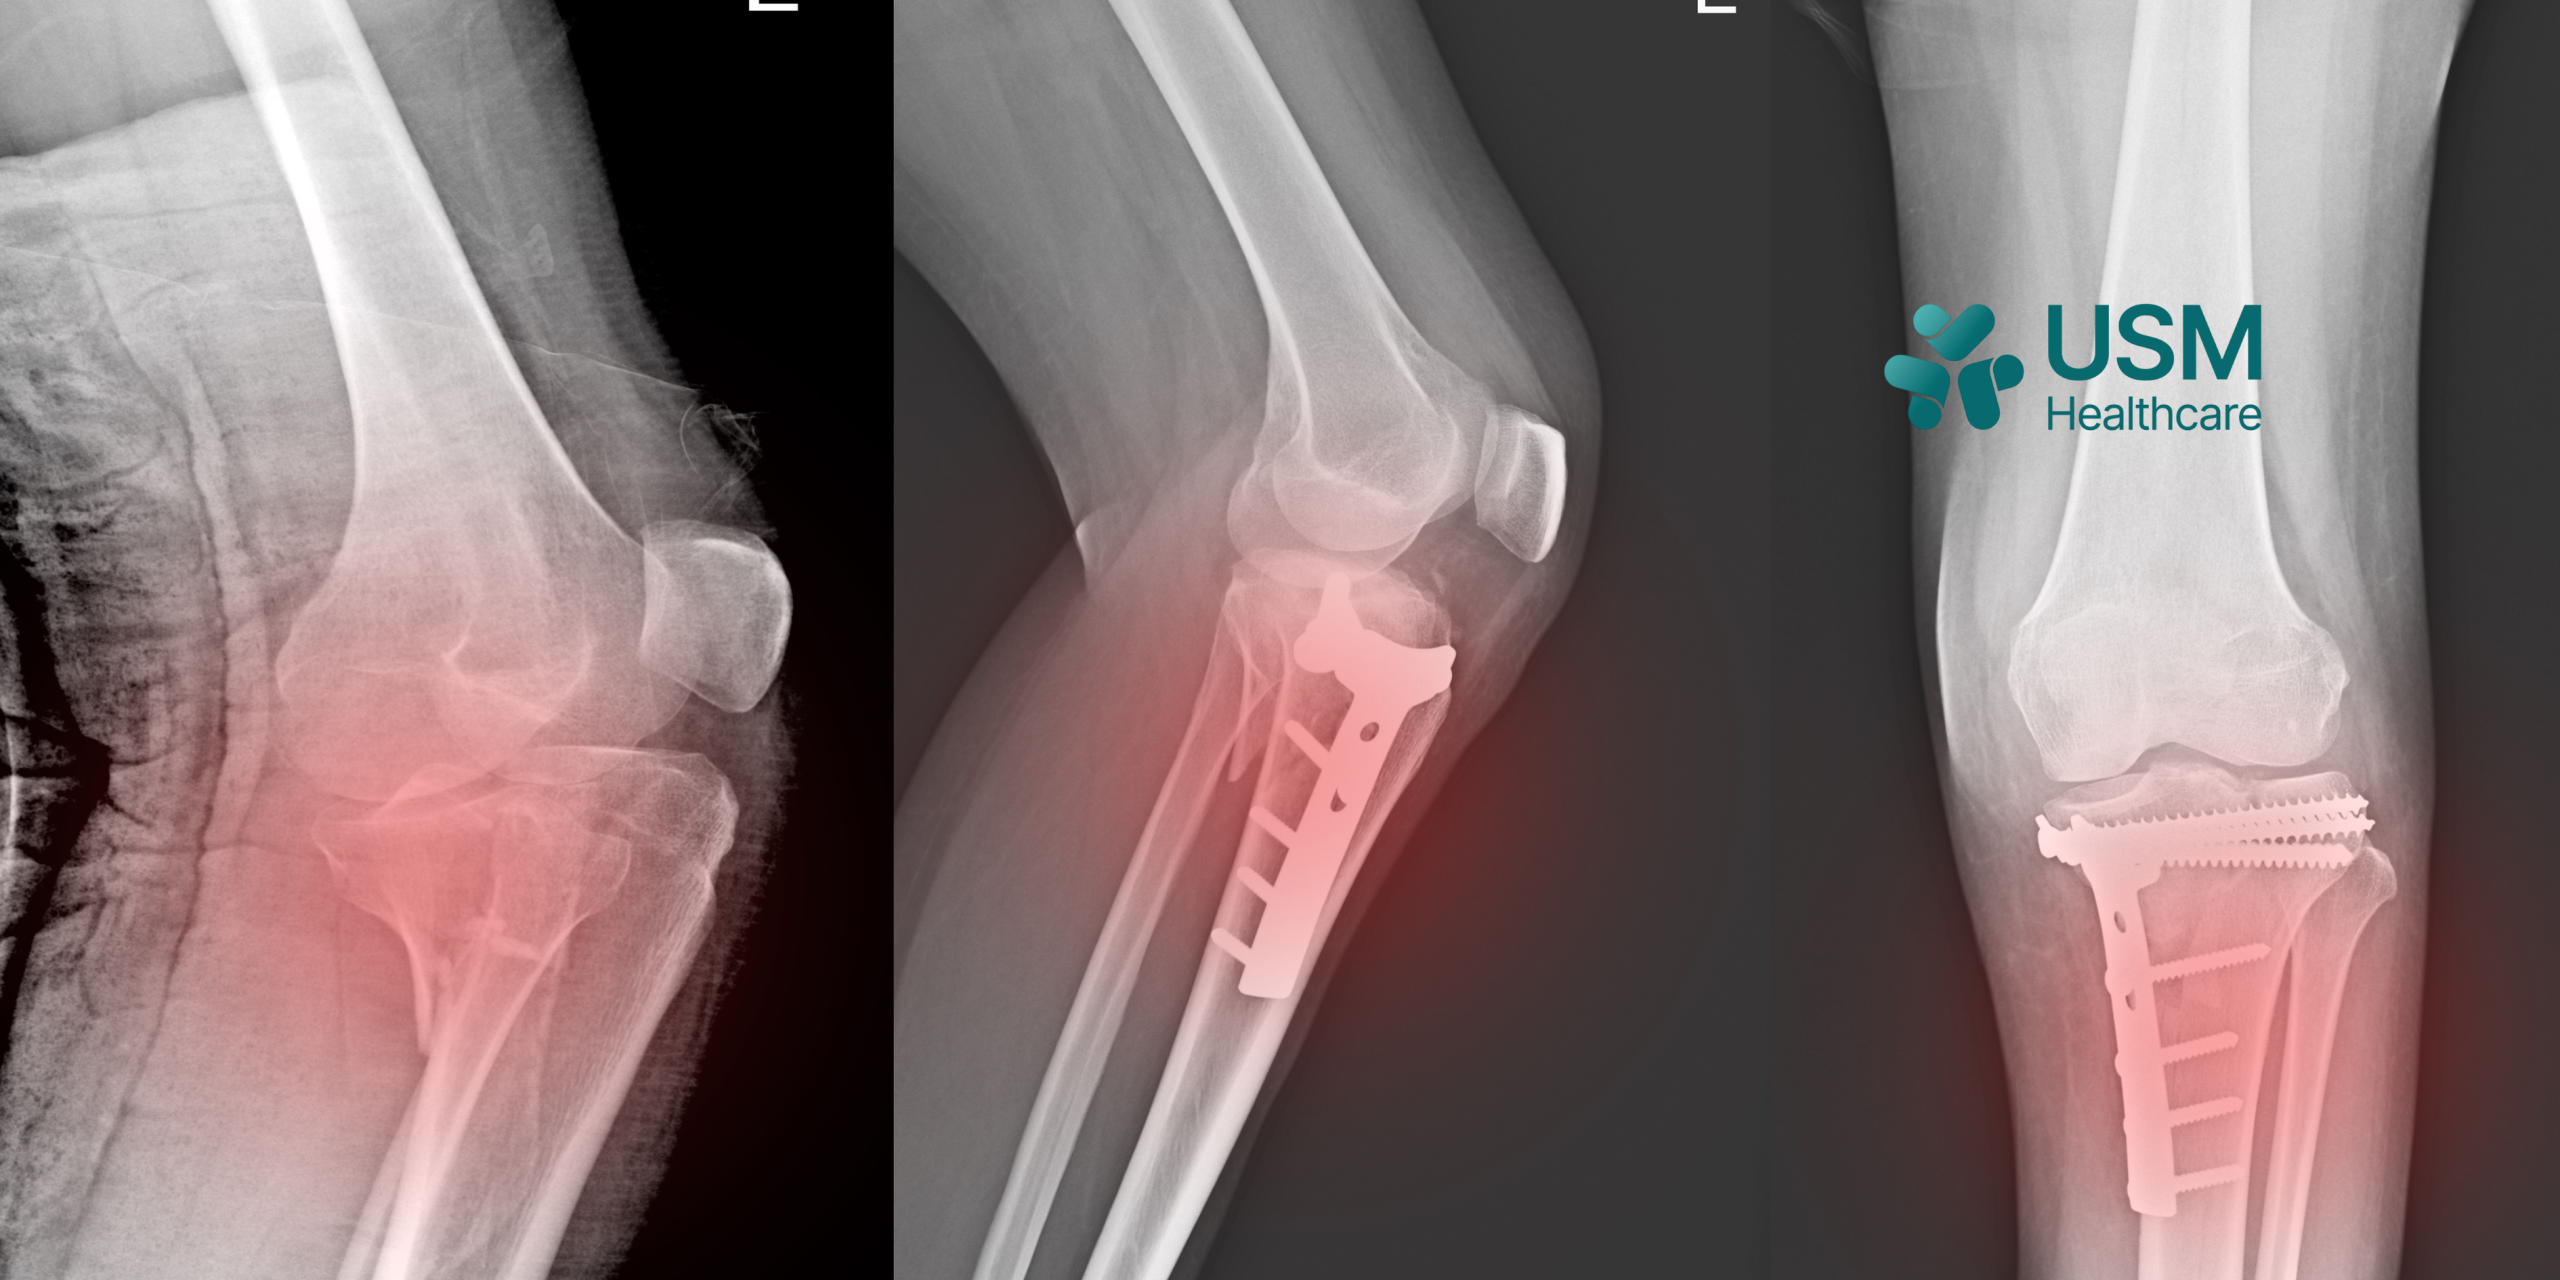

ASSESSING THE CLINICAL APPLICATION OF ARSENIO PLATE-SCREW SYSTEM IN ORTHOPEDIC & TRAUMATOLOGY TREATMENT